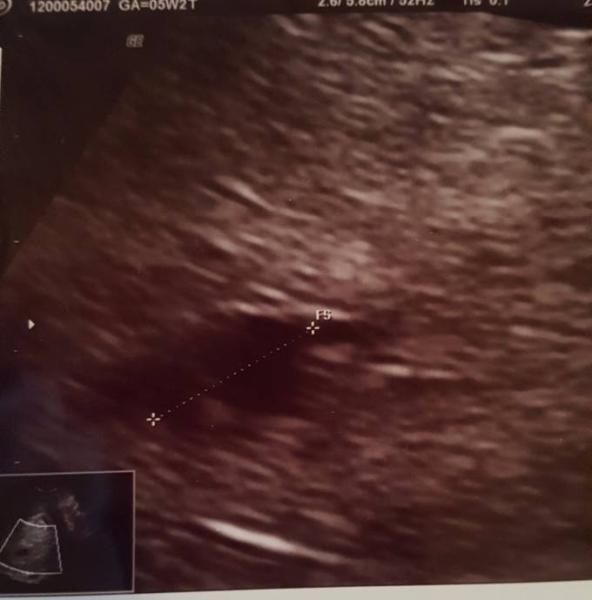

Hatte heute meinen ersten fa Termin... es sieht alles soweit gut aus... bin nun bei 5+5 und was konnte man sehen? Das kleine herzchen schlug schon... da war selbst die fä verwundert... bin so glücklich... Foto im Anhang